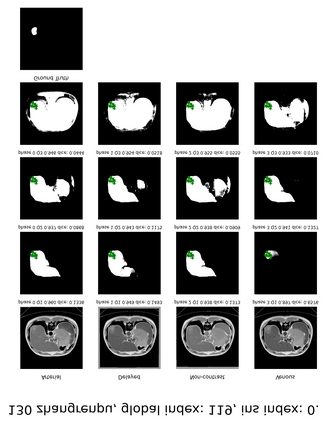

Learning to segmentation without large-scale samples is an inherent capability of human. Recently, Segment Anything Model (SAM) performs the significant zero-shot image segmentation, attracting considerable attention from the computer vision community. Here, we investigate the capability of SAM for medical image analysis, especially for multi-phase liver tumor segmentation (MPLiTS), in terms of prompts, data resolution, phases. Experimental results demonstrate that there might be a large gap between SAM and expected performance. Fortunately, the qualitative results show that SAM is a powerful annotation tool for the community of interactive medical image segmentation.